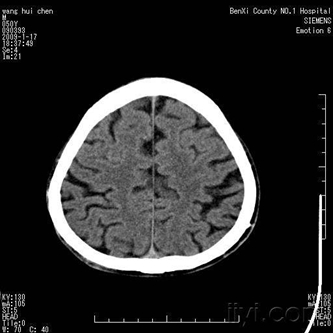

1.下列哪种方法为颅脑疾病诊断的基本方法: ( )

A.脑室造影 B.计算机体层 C.头颅平片 D.医学影像 E.脑血管造影